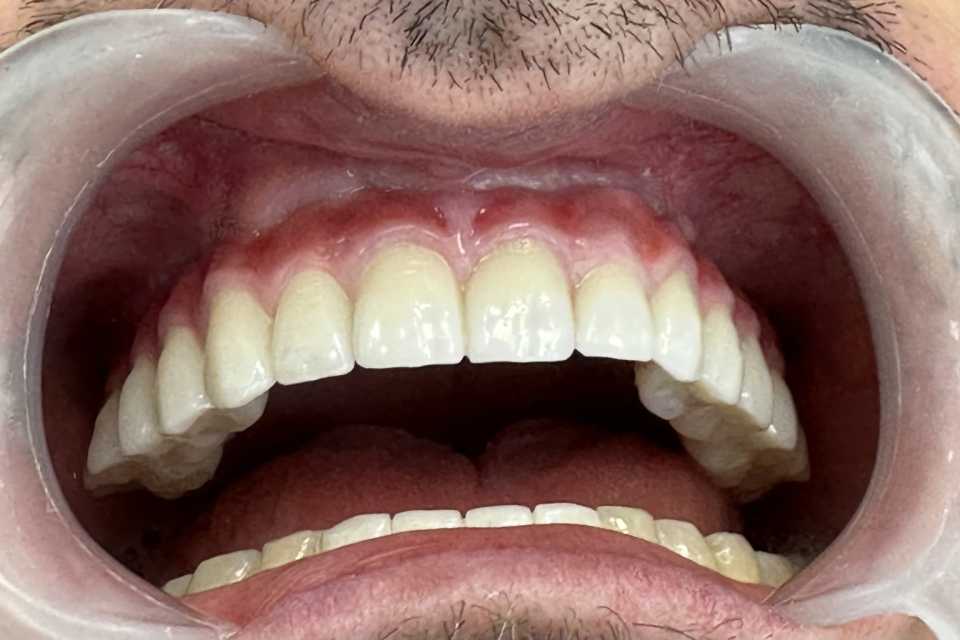

Pacient în vârstă de 39 de ani se prezintă în clinica noastră cu probleme de natură estetică și funcțională la nivelul maxilarului.

În urma consultului de specialitate, s-a decis extracția dinților parodontotici și a unei lucrări vechi, urmată de inserarea a 7 implanturi dentare Mega-Gen AnyRidge, cu adiții osoase și sinus lift bilateral. Implanturile au fost poziționate strategic pentru a permite o reabilitare protetică completă, formată din 14 dinți, asigurând astfel zâmbetul dorit de pacient.

Lucrarea protetică este fixă, înșurubabilă pe suport multiunit, realizată din ceramică pe suport de titan.